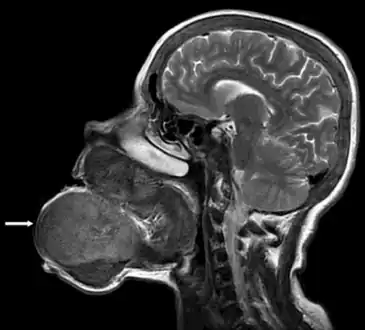

Image showed that the brown tumor originated from the mandibular and maxillar bones -

Micrograph of a brown tumor (left of image). H&E stain.